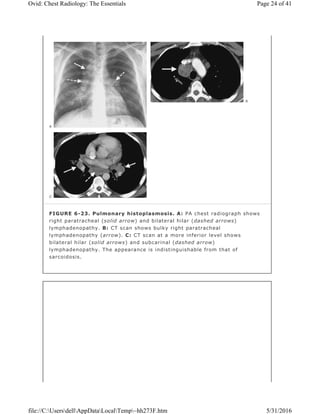

The most frequent infections that give rise to intrathoracic adenopathy are

caused by mycobacterial disease (most notably tuberculosis) and fungal disease

(particularly histoplasmosis; Fig. 6-23), each of which can occur without evident

pneumonia. Some patients develop a chronic progressive immune

response to dead Histoplasma capsular antigens, resulting in a condition known

as fibrosing mediastinitis. In this condition, nonmalignant fibrous tissue encases

and obliterates vasculature (arteries, veins, lymphatics) and airways in the

mediastinum (Fig. 6-24). Subcarinal and right paratracheal nodes are most

commonly involved. Calcification of nodes and simultaneous encasement of

airways and vasculature are characteristic CT findings of this disease.

FIGURE 6-23. Pulmonary histoplasmosis. A: PA chest radiograph shows

right paratracheal (solid arrow) and bilateral hilar (dashed arrows)

lymphadenopathy. B: CT scan shows bulky right paratracheal

lymphadenopathy (arrow). C: CT scan at a more inferior level shows

bilateral hilar (solid arrows) and subcarinal (dashed arrow)

lymphadenopathy. The appearance is indistinguishable from that of

sarcoidosis.